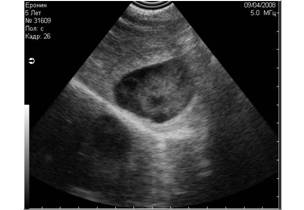

Рис. 11. Истинные тени, испускаемые скелетными структурами плода шелти на 36 день беременности. Первичными очагами минерализации являются череп и таз плода. На этом снимке мы видим две тени, испускаемые этими структурами. |